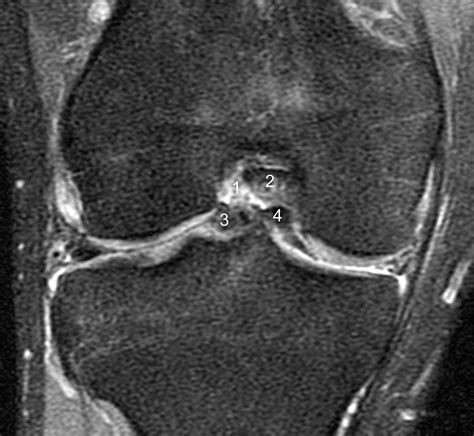

A Bucket Handle Injury is a specific type of meniscal tear that occurs in the knee. The meniscus is a C-shaped piece of cartilage that acts as a shock absorber between the thighbone (femur) and the shinbone (tibia). When a tear occurs in a way that the inner portion of the meniscus flips up into the joint, it is called a bucket handle tear because it resembles the handle of a bucket.

• MRI (Magnetic Resonance Imaging): To provide detailed images of the soft tissues, including the meniscus, to confirm the diagnosis.